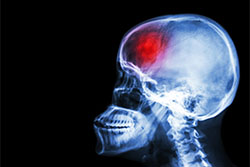

For Effective Treatment of Stroke, Speed Counts

StrokeIn the business world, you’ll often hear the phrase “time is money.” But in the medical world, particularly when it comes to treating victims of stroke, you’ll hear the phrase “time is the brain,” emphasizing that human nerve tissue is rapidly lost as stroke progresses, making immediate treatment critical.

A stroke is a "brain attack,” and is the leading cause of adult disability in the U.S. “The condition occurs when blood flow to an area of the brain is cut off. When this happens, brain cells are deprived of oxygen and begin to die, compromising such functions as memory and muscle control,” says Ann Hanley, MD, a neurologist at NewYork-Presbyterian Hudson Valley Hospital in Cortlandt Manor.

Strokes can be classified into two general types: an ischemic stroke is a result of a blood clot blocking a blood vessel carrying blood to the brain; less common is a hemorrhagic stroke, in which blood spills into or around the brain and creates swelling and pressure. This type of stroke is most often the result of hypertension.

Rapid and accurate diagnosis of the kind of stroke and the exact location of its damage is critical to successful treatment. For example, in cases of severe ischemic stroke, treatment involves the use of thrombolytic (clot-busting) therapy, but the medication must be administered within four hours of the onset of symptoms.

“The most recent intervention that has become the gold standard for treating acute ischemic stroke is mechanical thrombectomy (the surgical removal of clots that are blocking blood circulation), which must be performed within six hours of symptom onset,” says Dr. Hanley. She also notes that acute stroke treatment has evolved significantly over the past 20 years. Hemorrhagic strokes can often be managed medically as well but, at times, surgical options may be used depending on the site of the bleeding.